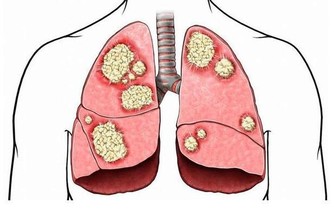

4.氯對人體有什麽危害?

答:氯氣對人體有嚴重危害,它能刺激眼、鼻、喉以及上呼吸道等。引起急性肺水腫及肺炎,濃度高時可麻痹呼吸中樞、出現「閃擊性死亡」。長期吸入低濃度的氯會引起慢性中毒,導致體內產生大量的自由基,加速人體衰老速度。主要病癥為鼻炎、慢性支氣管炎、肺氣腫、肝硬化、動脈粥樣硬化,甚至是癌癥。

9.為什麽說自來水燒開後危害更大?

答:將自來水加以煮沸,氯受熱後與水中有機腐質產生三氯甲烷等致癌物質,三氯甲烷將比自來水增加3~4倍,如果餘氯不能去除,我們每日所飲用的咖啡、茶或湯,經加溫煮沸飲用後;我們的體內即增加了3~4倍的致癌物。